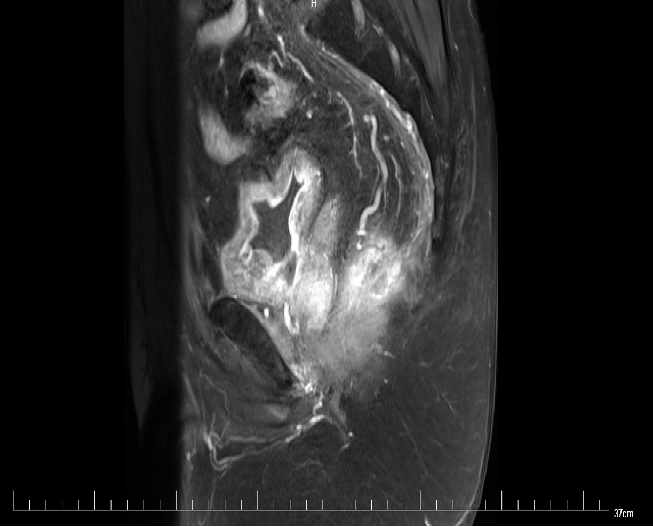

MR:1、直肠癌(T3可能),与右侧肛提肌关系密切,考虑1、炎性渗出粘连2、侵犯待排2、慢性膀胱炎3、前列腺增生。

2017-09 MR: